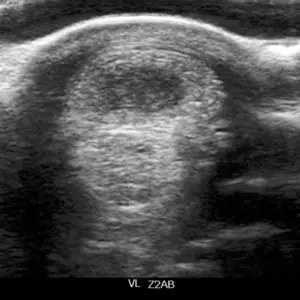

Die Lasertherapie wird zur Regeneration verschiedener Gewebe eingesetzt. So findet sie Anwendung in der Behandlung von beispielsweise Sehnen, Bändern und Muskeln, aber auch zur Förderung der Wundheilung bei schlecht heilenden Verletzungen.